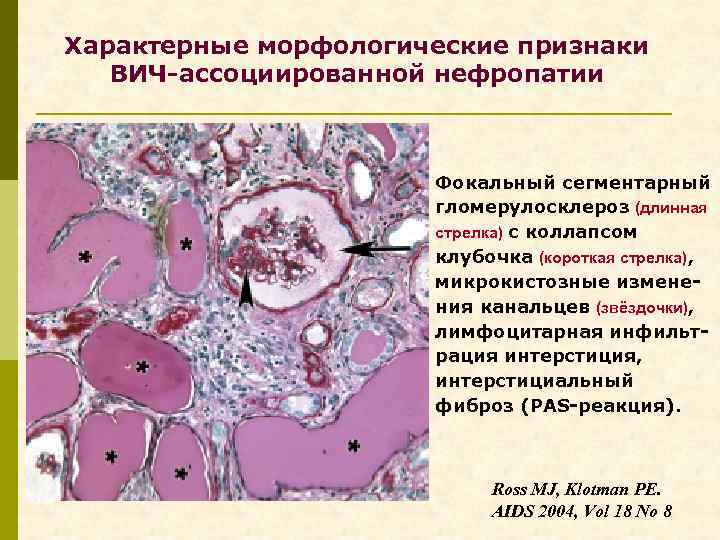

Характерные морфологические признаки ВИЧ-ассоциированной нефропатии Фокальный сегментарный гломерулосклероз, коллаптоидный вариант.

Характерные морфологические признаки ВИЧ-ассоциированной нефропатии Фокальный сегментарный гломерулосклероз (длинная стрелка) с коллапсом клубочка (короткая стрелка), микрокистозные изменения канальцев (звёздочки), лимфоцитарная инфильтрация интерстиция, интерстициальный фиброз (PАS-реакция). Ross MJ, Klotman PE. AIDS 2004, Vol 18 No 8